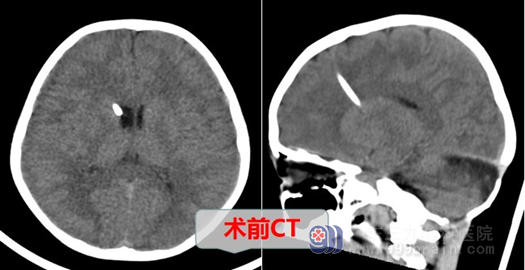

佳佳小朋友今年9岁,因不慎从高处摔落,昏迷不醒,在当地医院进行CT检查后发现头皮下异物外露。在当地医院急诊医生问询下得知曾有松果体肿瘤病史,考虑到进一步治疗,减轻小佳佳的痛苦,佳佳父母再一次找到了广东三九脑科医院。在经过了简单的问诊后考虑松果体肿瘤术后Ommaya管外露,现为进一步治疗入院。收入神经外十科诊断:1.ommaya管外露;2.松果体成熟畸胎瘤切除术后。

入院后经外十科欧阳辉教授团队,结合相关检查得出结论:患儿Ommaya管外露明确,拔除手术指征明确。术中注意要轻柔操作,保护好脑组织及血管,避免引起颅内出血。欧阳辉科主任指出:目前“1.Ommaya管外露;2.松果体成熟畸胎瘤切除术后”诊断明确。综合病情,有手术指征,如不手术,外露的Ommaya管会引起颅内感染,手术目的明确。必须尽行“Ommaya管取出术”,手术很快成功完成。